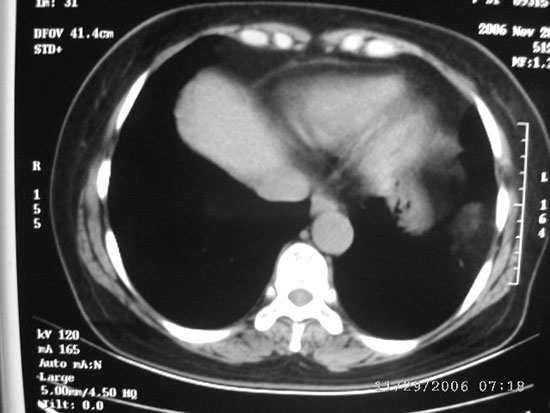

ct值-106

图象质量差,ct图片太少没有临床资料.猜出结果太伟大了

你用黑白模式拍啊.看不清,哪的ct值,密度都一样吗?脂肪瘤?

图像处理了一下,还是不很好!我觉得应该是脂肪瘤或者腹腔脂肪组织

ct图片少又差,还不如就胸片让人来猜,左胸腔包裹性积液.

脂肪组织   或膈疝

有可能是大网膜疝,往下扫两层看看.

ct图片少难度太大,我考虑1、左侧包裹性胸腔积液  2、炎性假瘤

考虑错构瘤

ct图片少难度太大,考虑1、左侧包裹性胸腔积液  2、炎性假瘤

图片少、质量不佳,难度大,考虑错构瘤。